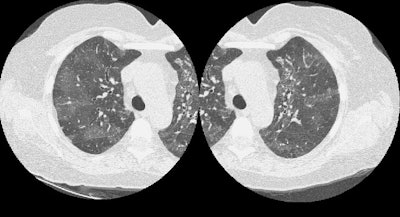

Mosaic attenuation:

A mosaic pattern is produced by the patchy distribution of areas of increased and decreased lung attenuation as shown in the case below.